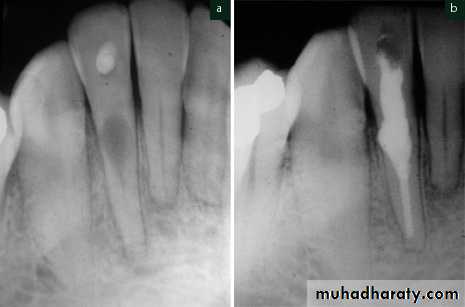

Radiographic findings—caries may be seen if extensive enough; a periapical radiolucency will be present; some cases may have evidence of previous endodontic treatment; occasionally may see a radiolucency within the tooth root indicating internal inflammatory resorption.

Key findings for diagnosis—there is a periapical radiolucency and no pain or only occasional “awareness” of the tooth.

Distinguish from primary acute apical periodontitis by the presence of a periapical radiolucency.

Distinguish from secondary acute apical periodontitis bythe lack of symptoms.

Radiographic findings—caries may be seen if extensive enough; a periapical radiolucency is present—this indicates chronic apical periodontitis has been present for some time; some cases may have evidence of previous endodontic treatment; occasionally may see a

radiolucency within the tooth root indicating internal inflammatory resorption.

Key findings for diagnosis—there is a periapical radiolucency, the pain is recent and severe; pain with pressure and on percussion.